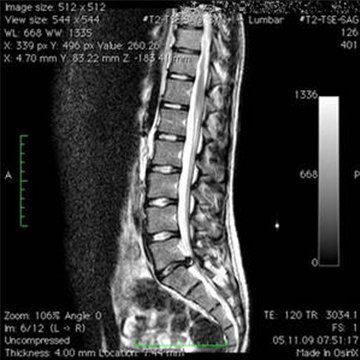

Comment diagnostique-t-on une hernie discale?

En plus du diagnostic clinique, une hernie discale est diagnostiquée ou confirmée à l'aide de l'imagerie à résonance magnétique (IRM).

Bandscheibenvorfall L5 S1 praeoperativ transversal Bandscheibenvorfall L5 S1 praeoperativ transversal